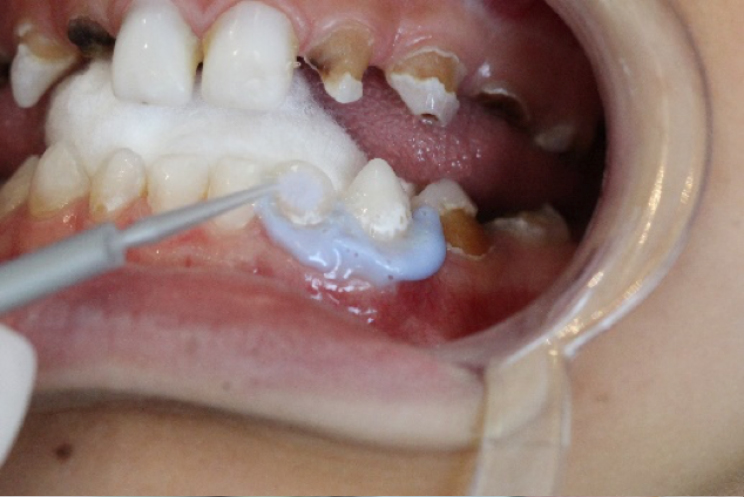

Inicialmente realizou-se a profilaxia com o uso de pasta profilática (sem flúor) e escova Robson. (foto 6)

Em seguida realizou-se o isolamento relativo com rolete de algodão e secagem dos elementos com jato de ar. Foi realizada barreira gengival e fotopolimerização da mesma. (foto 7, 8 e 9)